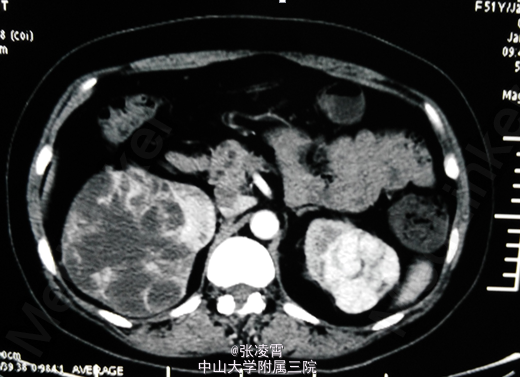

血常规 :血红蛋白浓度96g/L; 尿常规:白细胞计数 77.1个/ul; 腹部及盆腔平扫+增强:1.双肾多发占位,2.肝、胆囊、脾脏未见明显异常,3.盆腔未见明显异常。

1、双侧多发肾占位病变(肾癌?) 2、高血压II级 (中危组) 拟予口服索坦50mg qd口服一周后予行肾癌根治术。在口服索坦期间予行胸部CT发现有转移瘤。遂予取消手术。与患者及家属交代病情后,患者及家属考虑待其出院后商议后再考虑是否继续就诊。